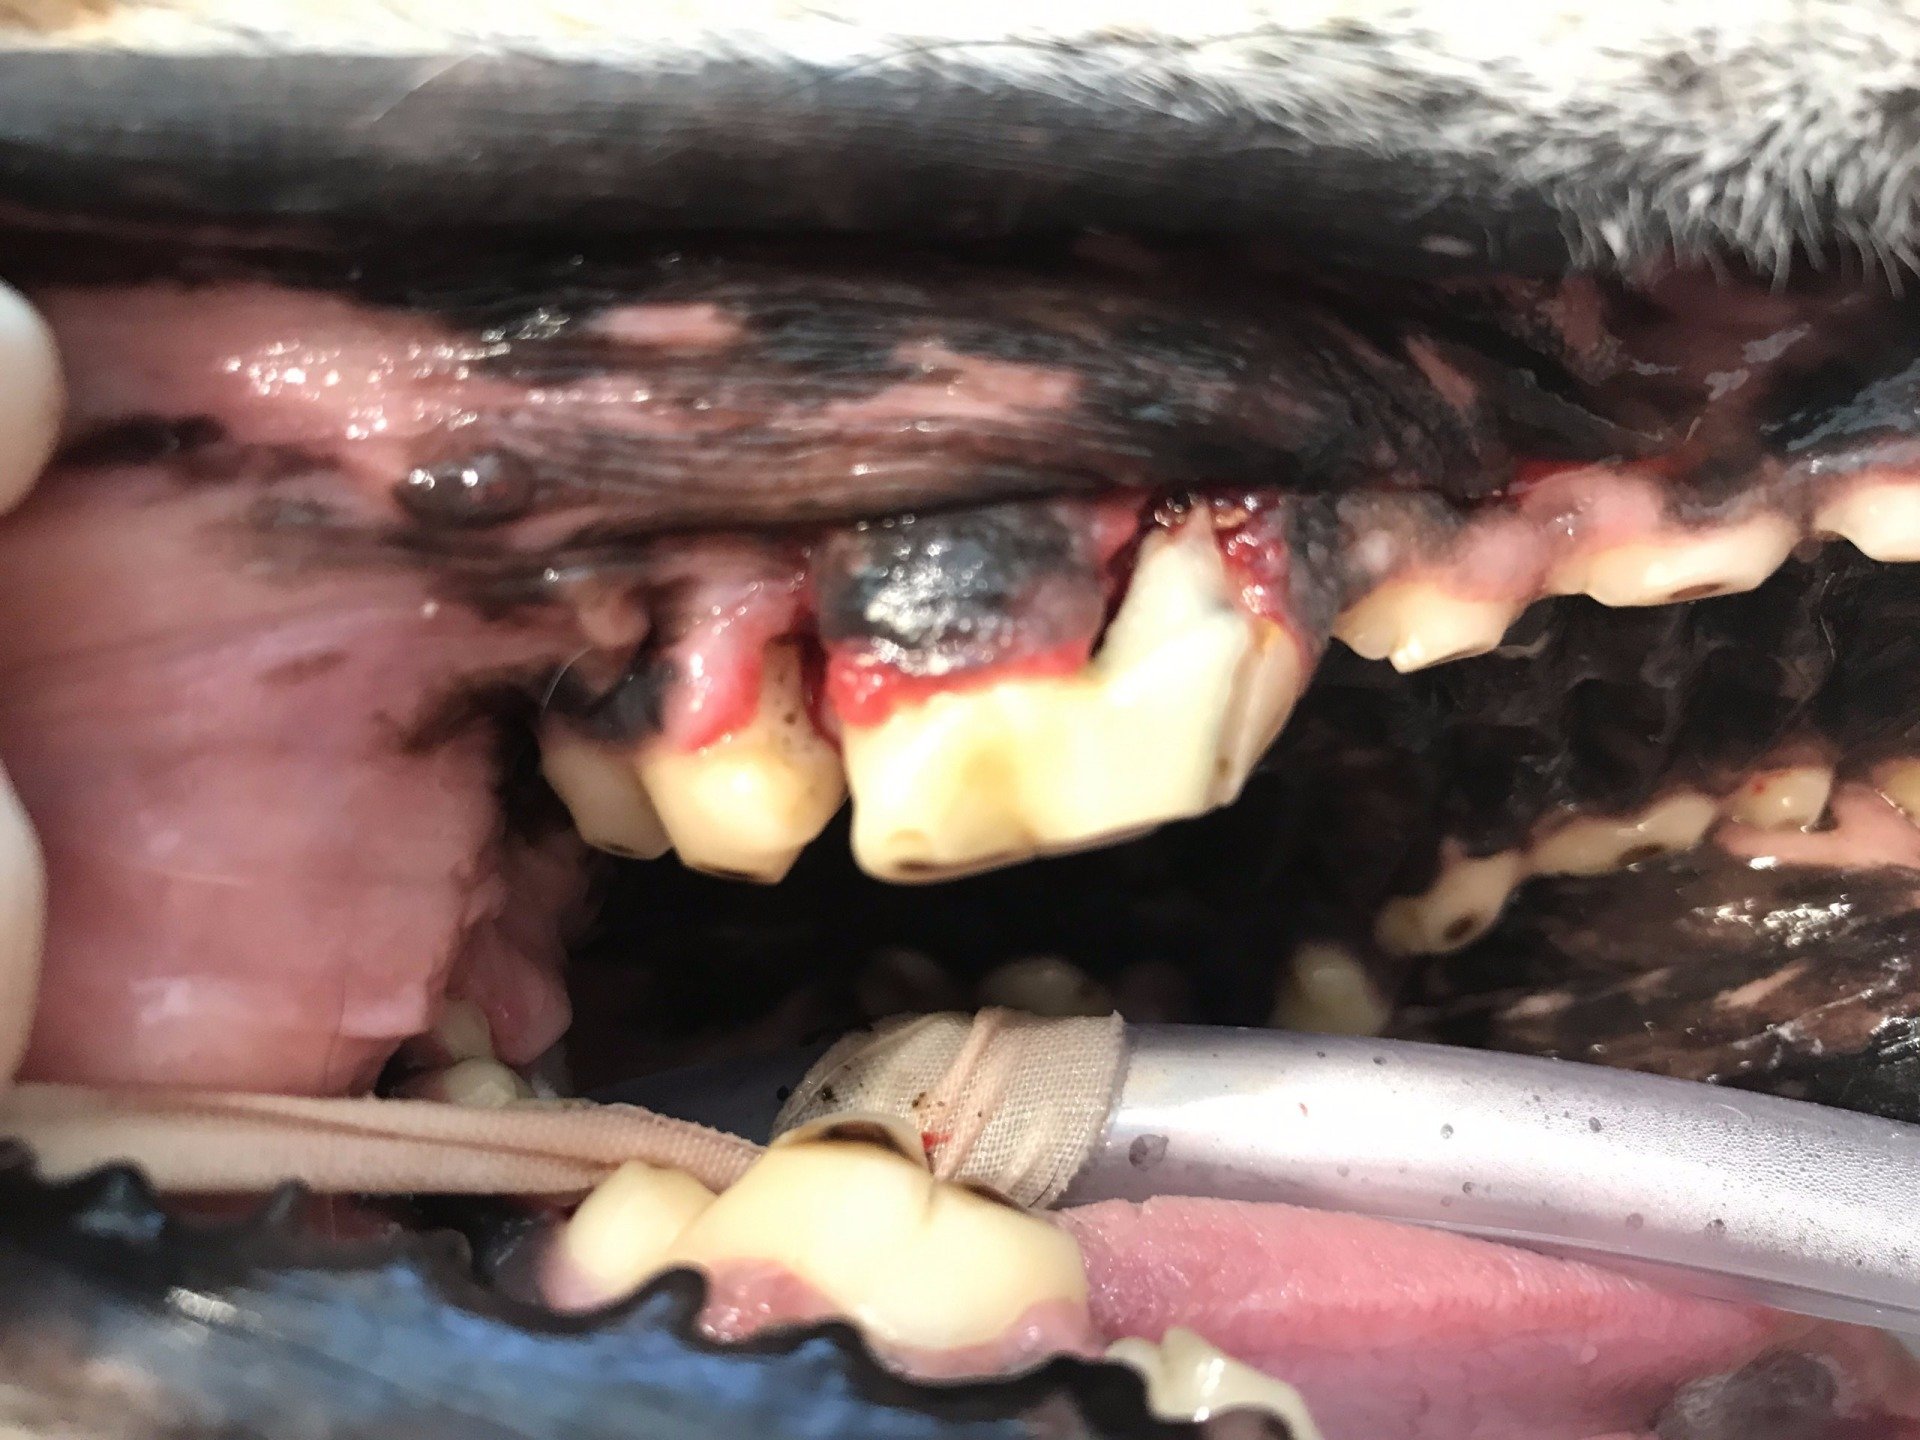

Een hond met ernstige Parodontitis

Op foto 1 en 4

zie je de kiezen in de kaak, ogenschijnlijk nog mooie elementen om te zien, maar

Op foto 3

zie je het resultaat na extractie van de kiezen van de linkerbovenkaak.

Deze hond heeft een ernstige vorm van parodontitis (ontsteking van het weefsel rondom een kies of tand) en is ooit begonnen als een gingivitis (tandvleesontsteking). Door het langdurig aanwezig zijn van een ontstekingsreactie door tandplaque is het bot langzaam weggetrokken. Deze chronische ontsteking is zeer pijnlijk en ook gevaarlijk voor andere organen in het lichaam. Preventie door poetsen en goede, regelmatige tandheelkundige behandelingen is de oplossing dit te voorkomen. Welke regelmaat van behandelingen nodig is, is per dier verschillend.